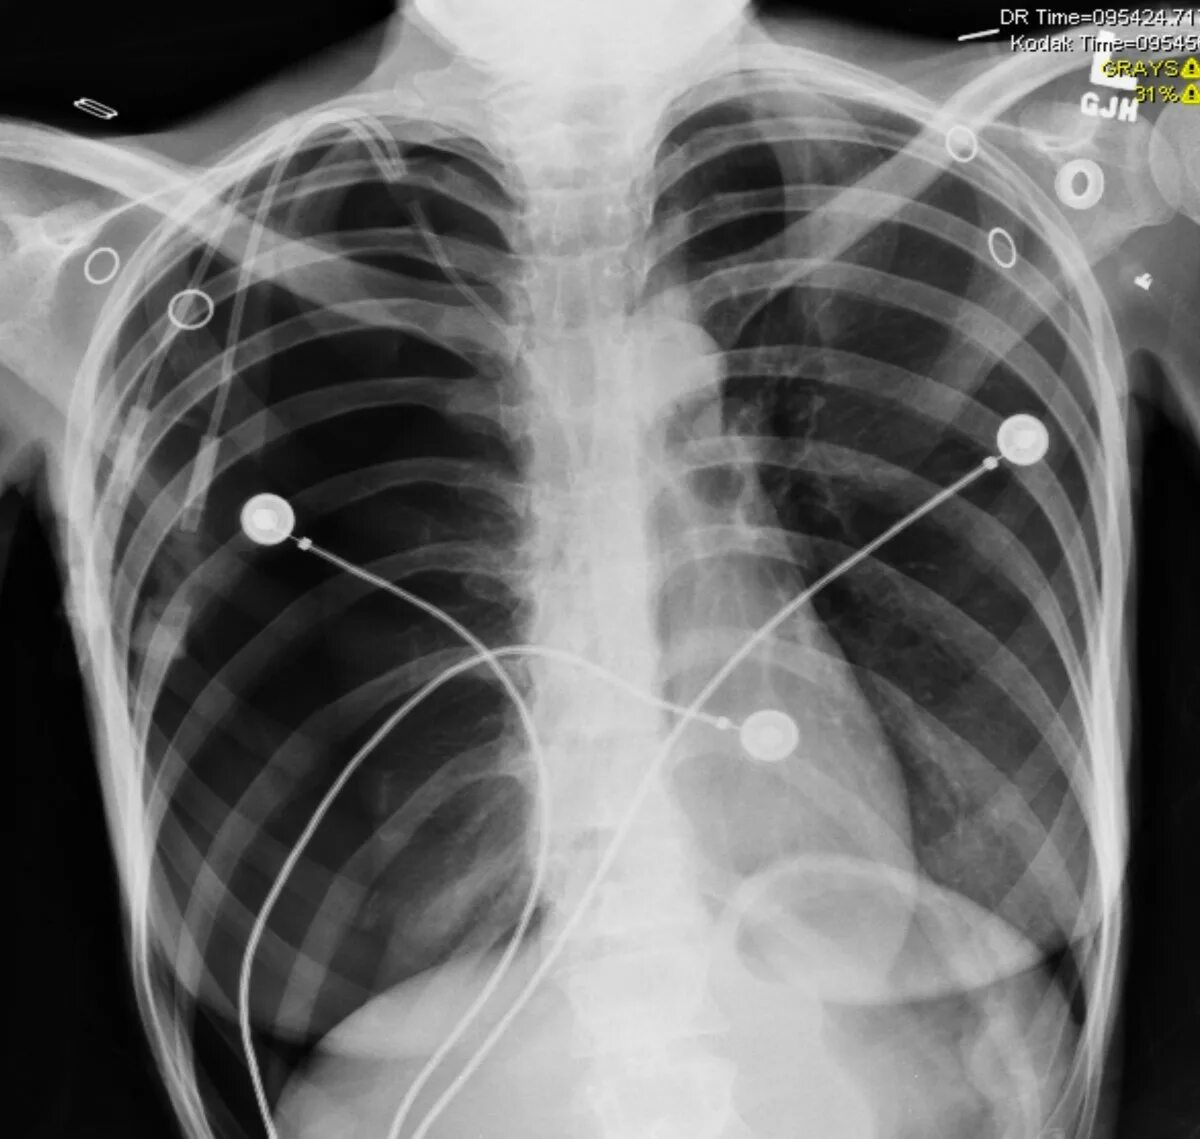

Ренген легких платно